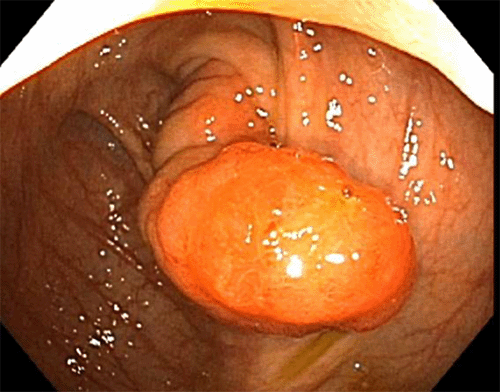

She underwent an EGD and colonoscopy, which was notable for a 30 mm polypoid appearing lesion coming from the appendiceal orifice (Figure 1) and an otherwise normal colon. Biopsies of the lesion showed fragments of colonic mucosa with hyperplastic change, fibrosis, crypt architecture distortion, and focal mild acute and chronic inflammation. A CT showed a tubular structure within the cecum measuring approximately 5 cm in length and 1 cm in width, concerning for an inverted appendix (Figure 2).

Figure 1. Colonoscopy Image of Inverted Appendix. Published with Permission

The vague abdominal pain and hematochezia exhibited in this case made an immediate diagnosis difficult. As such, she underwent a workup involving several modalities, which is common among cases of appendiceal intussusception in the literature.7,8,10‒12,16 Colonoscopy, while invasive, provided direct visualization of the mass and allowed for biopsies to be taken; ultimately, a CT was performed, which was highly suggestive of appendiceal intussusception. CT, ultrasound, and colonoscopy are the most commonly used modalities for modern assessment. However, barium studies were frequently used when such modalities were not readily available and typically showed a cecal filling defect.7,8 Given her persistent abdominal pain and inability to definitively rule out malignancy, she underwent surgical intervention, revealing the nature and etiology of her appendiceal mass. A gross examination of the specimen (Figure 4) identified this case as a type I, based on the McSwain classification.5